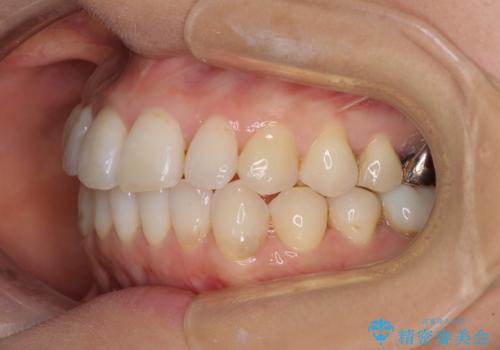

- 捻れた前歯と目立つ銀歯を気にして来院された患者様です。

歯列不正は軽微であったため、インビザライン・ライトにて改善することとしました。

左下大臼歯は根管治療が必要であったため、矯正治療前に根管治療を行い、その後矯正治療を行うこととしました。

矯正治療後には期にある銀歯を全てセラミッククラウンなどで補綴治療することとしました。

インビザライン・ライトによる矯正治療であったので、時間をかけずに治療を終えることができました。

口を開ける度に目立っていた銀歯もセラミックで自然な口元の印象となりました。